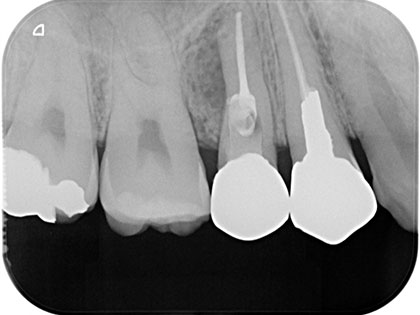

根管治療症例

感染根管治療を行った症例

前歯が腫れているとの事で来院され、感染根管治を行った患者様の症例になります